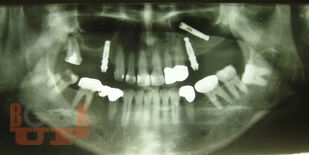

В учебном пособии рассматриваются вопросы клинико-рентгенологической диагностики хирургических осложнений дентальной имплантации, возникающие в интраоперационном и раннем послеоперационном периодах. Разделы пособия содержат клинические примеры осложнений, возникающих на хирургическом этапе имплантологического лечения больных. В отдельной главе, посвященной социологическому исследованию, приведены данные анкетирования врачей-стоматологов по проблемам имплантологического лечения, которые позволяют выявить наиболее острые проблемы, стоящие перед имплантологами, в том числе, пробелы в послевузовском образовании. Пособие иллюстрировано цветными фотографиями, облегчающими восприятие излагаемого материала.